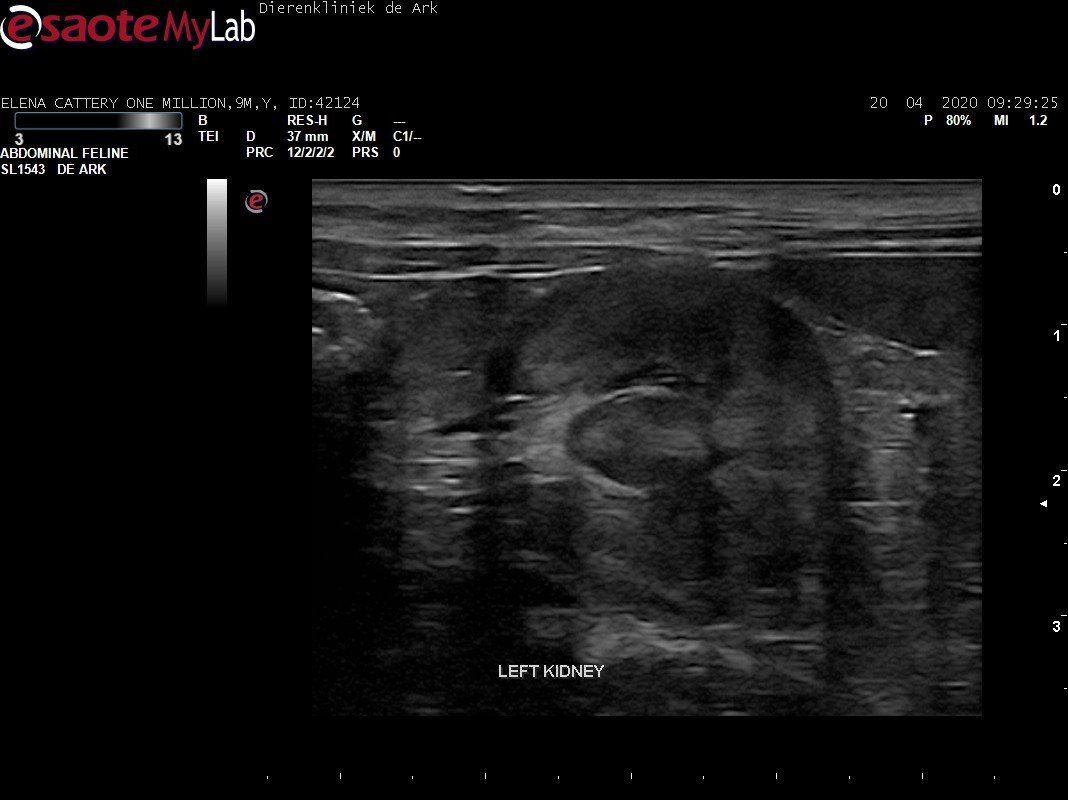

3,200 kg , echo en nieuw bloedonderzoek gedaan wat perfect ging door middel van gapabetine

Voor de garanties en om recht te hebben op medicatie bij herval eist Mutian diverse onderzoeken en controle momenten. Dit zijn bloedonderzoeken maar ook zoals hieronder te zien is echo's. Elana is volledig gecontroleerd op afwijkingen, gelukkig waren de echo's goed.

Ook de bloeduitslagen waren in orde, we kregen groen licht om te stoppen met behandelen en de wachtperiode in te gaan.